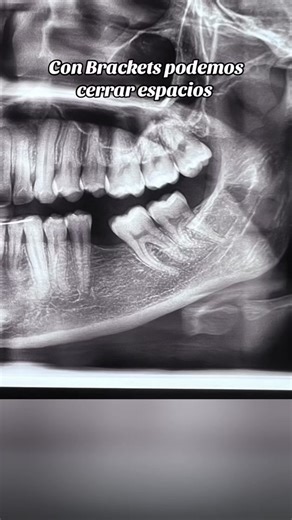

- Brackets

Braces - Brackets